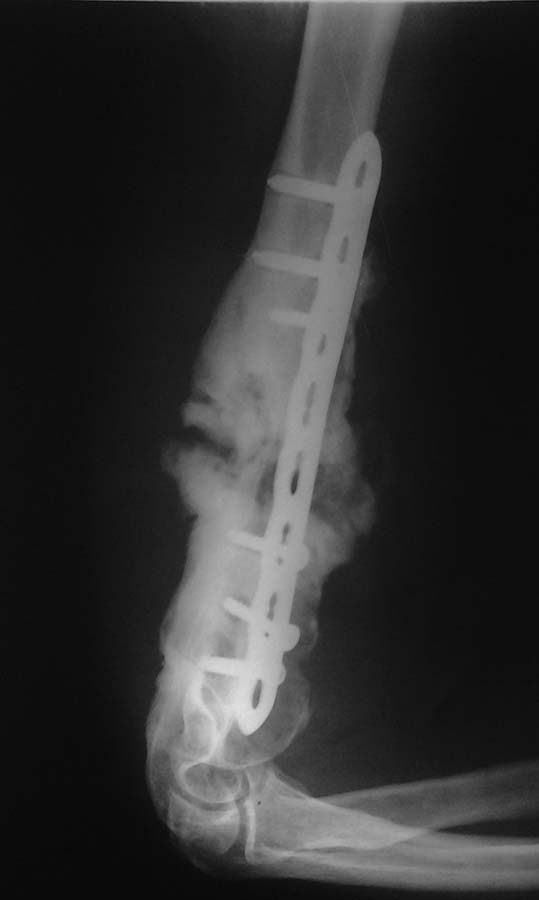

пациент (мужчина 32 лет) пришел удалять пластину, и сообщил что травма 1

год назад, выполнен синтез, через 2 мес. появились боли, которые стихли

1,5 мес. назад. повторные травмы отрицает. объм движений в локтевом

суставе удовлетворительный: сгибание до угла 40, разгибание 170-175,

явлений неврита нет, имеется патологическая подвижность в н/3 плеча.

Уважаемые коллеги выскажите свое мнение по поводу данного случая и что

бы вы предложили пациету. Большое спасибо.